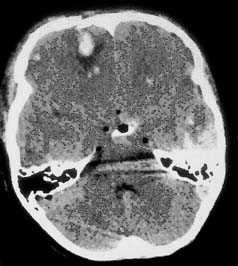

Компьютерная томография при травматическом повреждении головного мозга.

Применение компьютерной томографии в нейротравматологии существенно изменило представление о возможностях диагностики различных черепно-мозговых повреждений. КТ является в настоящий момент «золотым стандартом» - наиболее информативным методом обследования больных с черепно-мозговыми травмами и позволяет в самые короткие сроки судить о механизмах возникновения поражения мозга, его характере, распространенности, выраженности отека и дислокации мозга, а также динамике этих изменений.

Компьютерная томография является очень важной методикой в оценке травмы головы, и относится к методам первого выбора. Исследование проводится очень быстро (менее одной минуты). КТ высоко чувствительна к крови и хороша для изучения костей, воздуха (пневмоцефалии) и рентгенологически плотных инородных тел. Для обеспечения максимальных диагностических возможностей томограммы при черепно-мозговой травме должны быть рассмотрены в разных режимах для выявления первых признаков инсульта, оценки паренхимы, крови и кости/воздуха/жира.